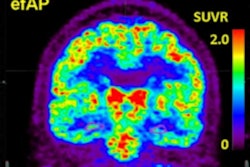

Building on recent work that enabled calculation of molecular PET measurements in tau-vulnerable convolutional temporal lobe anatomy, the researchers developed an automated anatomic sampling method to quantify tau signal on PET exams. They then applied their method to PET exams of 443 adult participants from several observational studies of people with Alzheimer's disease. These patients encompassed a wide range of ages, levels of beta-amyloid burden, and degrees of clinical measurements, according to the researchers.

The investigators found that tauopathy initially emerged near the rhinal sulcus in clinically normal people. In a subset of 104 participants who had longitudinal two-year follow-up data, the researchers also observed beta amyloid-associated spread of tau from this site to the nearby neocortex of the temporal lobe, followed by the extratemporal regions. Furthermore, subsequent elevation of tau in the temporal neocortex was associated with age, beta-amyloid, and apolipoprotein E status.